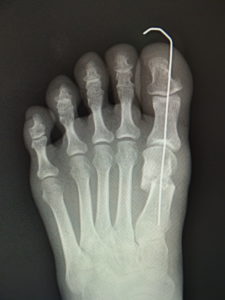

手術前 手術後4年

私は、ミッチェル変法ないしハモンド変法を行います(図6,7)。前日入院、腰椎麻酔(当日のみ臥床となります。)で一時間ほどの手術です。中足骨で骨切りを行い、長さも調節(多くはエジプト型足なので幾分短縮します。)しながら向きを矯正し、骨切り部をワイヤーで固定します。母趾内転筋の切離や、母趾外転筋の移行を検討します。中足骨頭部の種子骨を、正しい位置に戻して縫合します。術後は念のため、3週間ほど短いソックス型のギプスを装着しますが、術翌日から歩行訓練などの理学療法を行います。1ヵ月半ほどで骨癒合します。骨癒合が得られなかった症例はありません。2~3か月で普通に靴が履けます。入院期間は相談して決めればよいのですが、最短なら抜糸まで10日間、或いはギプス固定期間の3週間などが目安となります。

最近では、原則として固定ワイヤーは経皮的の一本のみとし、ワイヤーの先端は皮膚の外に出ているので、抜く時(術後3週間目)の患者さんの負担はほぼありません。こうすることによるデメリットはなく、むしろ術後成績は良くなっています。

(図6)

手術前 手術後

(図7)

真田理事長による手術の様子。外反母趾|症例 (左から 手術前、手術後、ワイヤ抜去後)